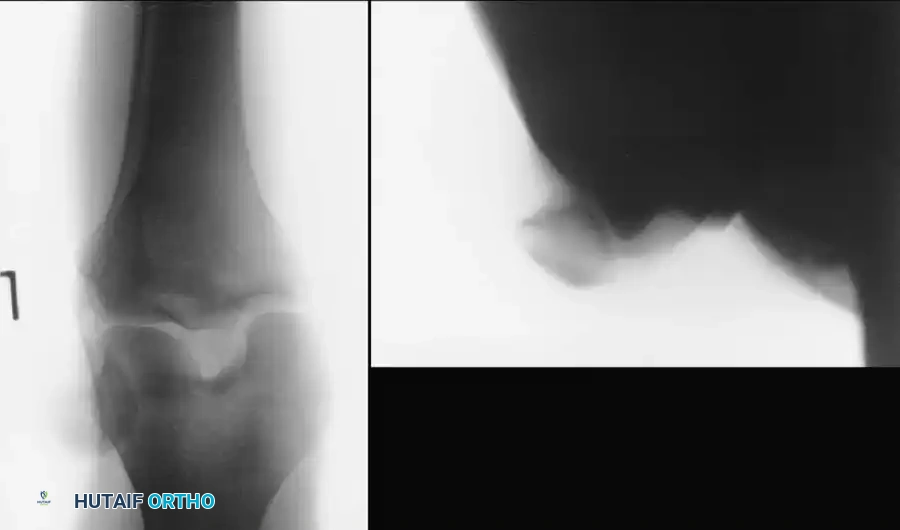

Fig. 57-1 Patellar dislocation. A, Anteroposterior view. B, Sunrise view.